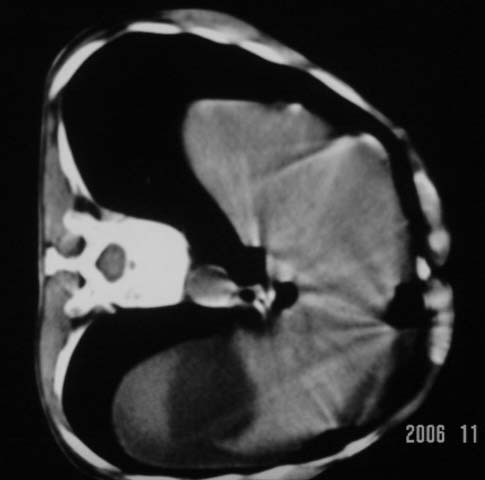

仰卧位见:肝前间隙及肝脾间隙内可见新月形气体密度影,边缘清楚,侧卧位见气体随体位改变而移动,ct值约-929hu。膈下、肝下间隙及部分肠间隙可见液性密度影。考虑:1、上腹部空腔脏器穿孔,以胃穿孔可能性大。2、少量腹水。

仰卧位见:肝前间隙及肝脾间隙内可见新月形气体密度影,边缘清楚,侧卧位见气体随体位改变而移动,ct值约-929hu。膈下、肝下间隙及部分肠间隙可见液性密度影。考虑:1、上腹部空腔脏器穿孔,结合临床,首先考虑胃穿孔可能性大。2、少量腹水

肝前间隙及肝脾间隙内可见新月形气体密度影,边缘清楚,侧卧位见气体随体位改变而移动,

支持消化道空腔脏器穿孔(腹腔内大量游离气体影,小网膜囊内亦见气体影),少量腹水。